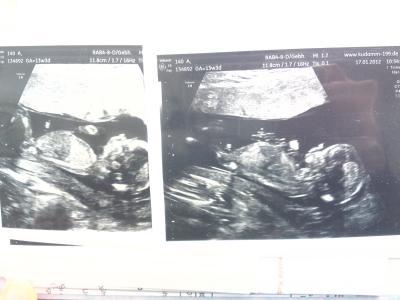

mit etwas verspätung...war ja am dienstag zum ersttrimesterscreening und alles ist super!! :))) mein et wurde jetzt wieder um 3 tage vorverlegt auf den 18.07. ... Was man da alles sehen kann ist echt faszinierend! Hab wunderschöne bilder bekommen...eine dvd hab ich selber mitgenommen und ganz nett gefragt, ob er mir die untersuchung aufnehmen würde und er hats wirklich gemacht...ich meine für umsonst - wer macht das schon? Also das zentrum für prenataldiagnostik am berliner ku'damm ist echt nur zu empfehlen!!! Und auf eine frage ob er schon sehen kann was es wird, meinte er zu mir, wenn ich da was sehen kann, dann kann ich es mir ja denken...er sagte, er darfs mir aus gesetzlichen gründen nicht sagen. Ich würde sagen eindeutig junge :)) Naja, ich hänge mal ein bild mit an...mal sehen was ihr dazu sagt :))) Lg

Bild zu bericht vom ersttrimesterscreening... - Forum für Juli - Mamis

Eindeutig Junge.... :-D Herzlichen Glückwunsch.... Und super schöne Bilder....

Hä bin ich blind??? wo kann man auf diesen bildern sehen das es ein junge wird?? ich versuche da echt was zu sehen abe rich sehe nix.... ahhhhhhh kann mir nicht mal jemand nachhilfe in sachen ultraschall bilder geben... glg

schau mal auf dem rechten bild, da wo die beine anfangen, zeigt ein schniepel nach oben :))) hab nochmal das bild in größer mit rangehangen... Lg

der kleine schnipel da?? ha jetzt konnte cih es auch sehen es ist doch nicht hopfen und malz verloren bei mir